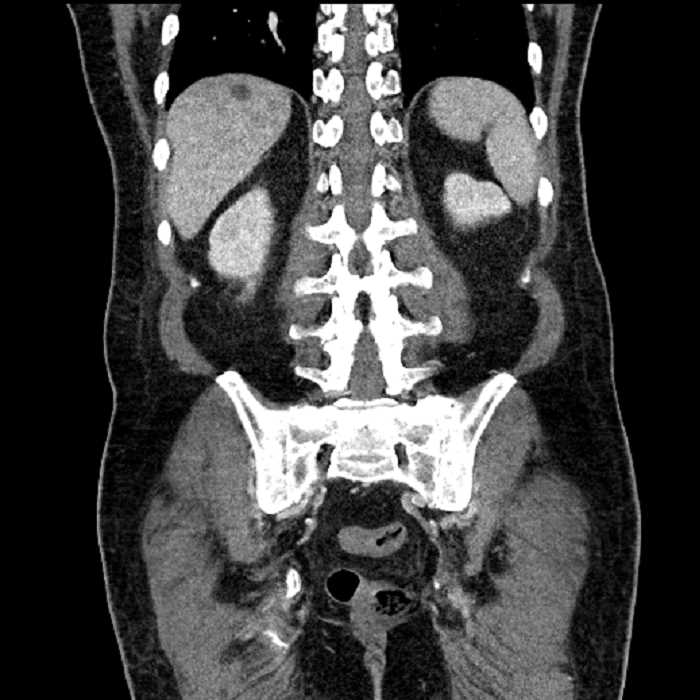

• Large fluid density structure in hepatic segments 7 and 8 measuring 10 x 7 x 7 cm with internal septation and circumferential ill-defined low density compatible with edema

• Peripherally enhancing subcapsular collections along the anterior margin of the left hepatic lobe measuring 3 x 1 cm and 2 x 1 cm

• Clearly marginated fluid density structure in segment 7 and several other scattered tiny hypodensities, which likely represent cysts

• Hepatic abscess

Acute sigmoid diverticulitis complicated by a small contained perforation and a large abscess in the right hepatic lobe. Additional small subcapsular abscesses along the anterior margin of the left hepatic lobe.

• The classic CT imaging appearance is a double target sign with internal low density surrounded by an internal enhancing rim (capsule) and a low density external rim (edema)

Hepatic abscess showing the double target sign with low density internally surrounded by a thin inner enhancing rim (red arrow) and ill-defined outer low density rim (yellow arrow). Blue arrow indicates an internal septation. Red arrows: additional smaller subcapsular abscesses. Red arrow: focal contained perforation associated with diverticulitis.